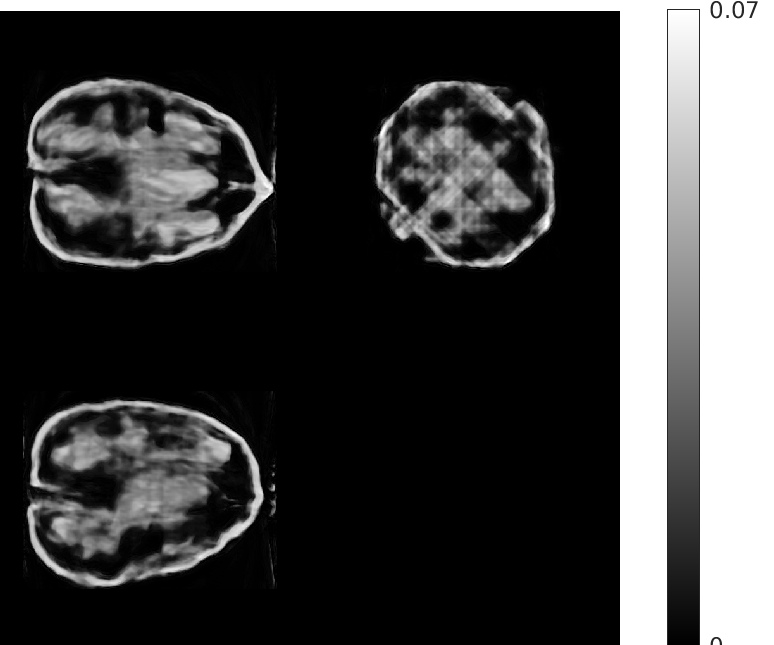

Fig. 5 shows walnut 1 from our test dataset being progressively reconstructed from 8 projections across the stages of our algorithm; as the stages progress, more features are restored in the reconstructed walnut, until the improvements become incremental. The residual streaking artifacts outside the walnut are mitigated in the reconstructions from the third and fourth stages.

| Stage 1 | Stage 2 |

![]() |

| (a) (MAE: 0.32) | (b) (MAE: 0.29) |

| Stage 3 | Stage 4 |

| (c) (MAE: 0.27) | (d) (MAE: 0.26) |